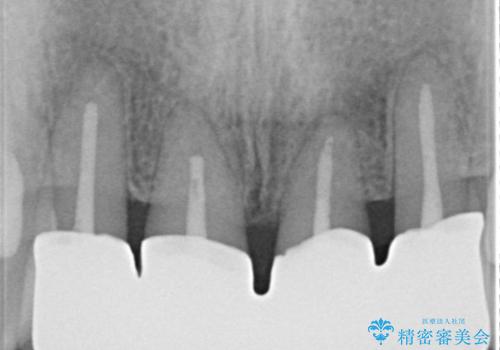

侵襲性歯周炎。前歯の歯周補綴

再生治療後、歯周補綴を行っております。

(根管治療はDr河野にて施術)

歯周病が進行してしまった歯に対し、再生治療および歯周補綴を行うことで歯周組織の安定を得ることができました。